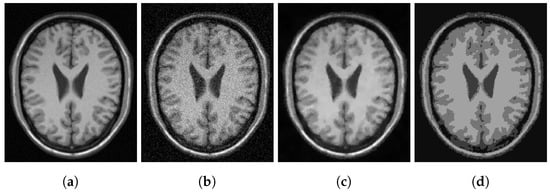

In Figure 3, Figure 4 and Figure 5, we show some examples of multiphase segmentation on MRI images of the brain. In all cases, we add Gaussian noise with mean 0 and standard deviation 17 and run the noisy image as input to both for all models but the CRCV model (as this is a two-phase model only). The output is then given as input to the k-means algorithm with . We show the clustering output in the final column of the relevant figures. We see that the segmentation result of our model is better at finding some of the finer edges; for example, the white matter segmentation from our model is in general more detailed than the segmentation from the competing ones.

Figure 3.

MRI segmentation: (a) Clean image. (b) Noisy image used as input to the models. (c) Output of CCZ. (d) CCZ after thresholding. (e) Output of CNC. (f) CNC after thresholding. (g) Output of T-ROF. (h) T-ROF after thresholding. (i) Output g of our model. (j) Output of our model. (k) Output of our model. (l) Ours after thresholding.